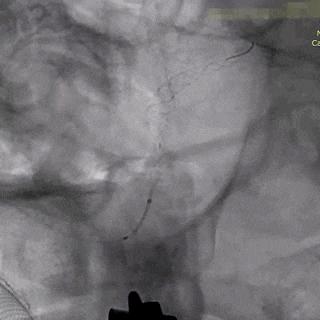

术后即刻造影。

术后重建。